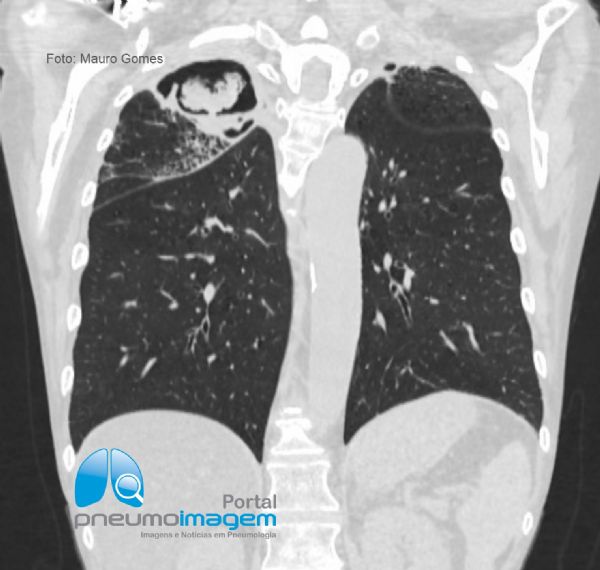

Corte coronal demonstrando o aspergiloma presente no lobo superior direito apresentado na imagem anterior.

Coronal section demonstrating the aspergilloma present in the right upper lobe presented in the previous image.